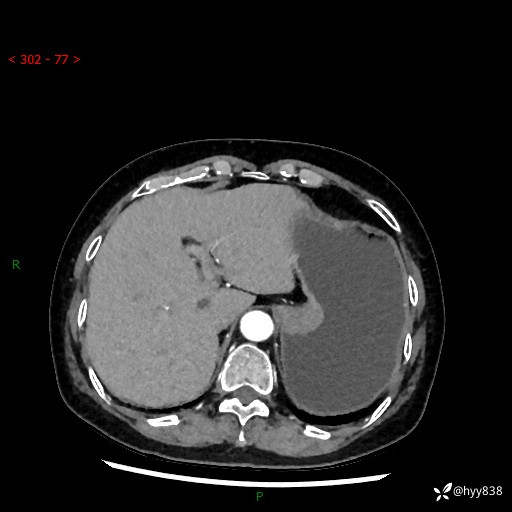

辅助检查:CT

胃CT平扫+增强(动脉期+静脉期)

三期CT值:46hu 58hu 75hu